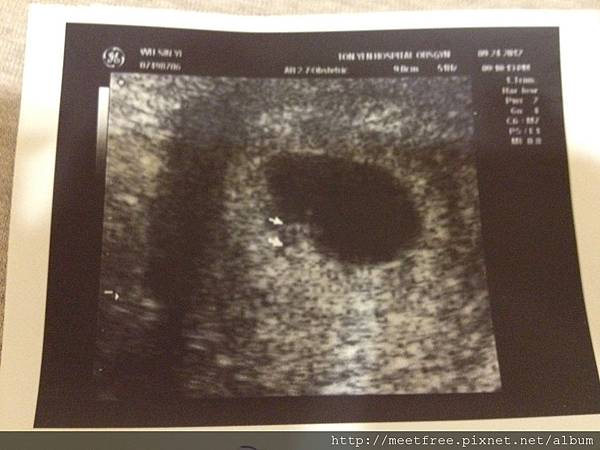

• 【媽咪日記】-羊膜穿刺

17W1D2012/12/04 Thu.(二)

距離上次產檢還不到一個月,主要是來做羊膜穿刺,

原本以為只要把作檢查的單子遞交出去,就等醫生來操刀了,

到了報到櫃台卻說照一般產檢流程><

(繼續閱讀...)